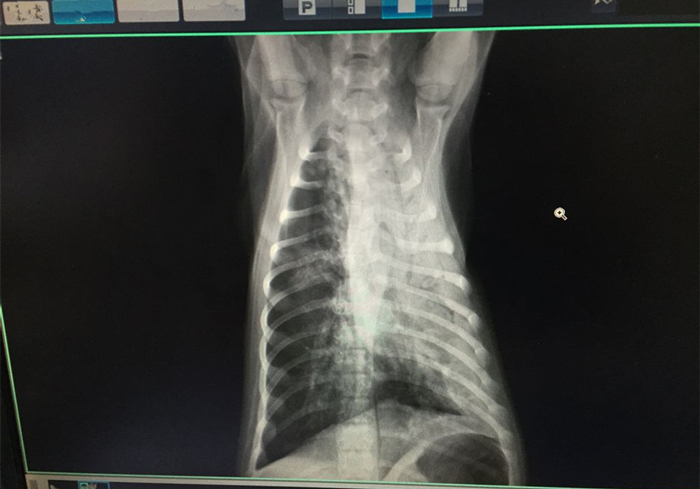

对于宠物医生的小心翼翼,铲屎官不以为然,拒绝了后续检查的建议。等到两个月后,医生就见到铲屎官一脸慌张地抱着狗狗就医。这回狗狗呼吸急促、声音浑浊,已经好久没有吃饭了。医生对狗狗做出了一系列的检查,最后在病历上写上了判断:纤维素性肺炎。

犬纤维素性肺炎,又称为犬大叶性肺炎,是狗狗支气管和肺泡内充满了大量纤维素蛋白渗出物为特征的急性肺炎。是属于一种急性或亚急性的疾病,发病速度极快,且死亡率极高。

当狗狗患上纤维素性肺炎时,病变会先始于局部的肺泡,然后迅速波及整个肺脏。因为临床特征主要为稽留热型,所以在狗狗的鼻腔内会出现铁锈色的鼻液,,这种铁锈色的鼻液因为是红色,所以在铲屎官的眼中看来,就会将其和鼻血混淆。

除了鼻腔中会放出铁锈色鼻液以外,狗狗患上纤维素性肺炎后,还会出现食欲减退、精神不振、咳嗽等症状,如果铲屎官仔细观察,可以发现它们会咳出大量的粘痰,并且能够发现它们体温上涨,呼吸时会发出浑浊的声音。